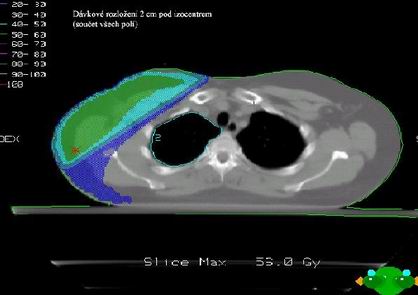

Dvě tangenciální hrudní pole

většinou s klíny

A jedno přímé pole nadklíček + boost axilla Pa pole (8 Gy)

Společné izocentrum pro všechna pole